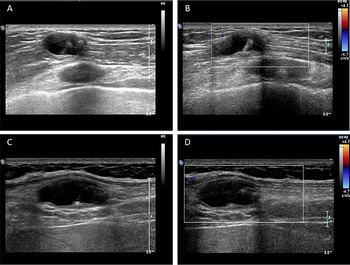

The routine laboratory blood tests, including eosinophil and lymphocyte count, were completely normal apart from the elevated inflammation markers (C-reactive protein and neutrophil count). Schistosomes, Clonorchis sinensis, Echinococcus granulosus and Toxoplasma gondii antibodies were negative in his serum, as were Cryptococcus capsular antigen and next-generation sequencing results from cerebrospinal fluid. Multiple intracranial nodules affecting the supratentorial and infratentorial cerebral parenchyma were shown in detail on CT and MRI of the head, indicating possible intracranial parasitic infection (Fig. 1). Ultrasound scan confirmed the presence of 2 palpable and soft masses located in muscles, which were approximately 19 × 8 × 15 mm3 under the right chest wall and 26 × 10 × 19 mm3 under the right midaxillary line (Fig. 2). A subsequent biopsy of the mass (Fig. 3) showed larval-like tissue, peripheral fibrous tissue hyperplasia, lymphocytic infiltration and hyaline degeneration. The patient was probably diagnosed with taeniasis and cysticercosis and treated with oral albendazole (400 mg, twice daily) over 2 weeks. Hydrocortisone 50 mg was provided 2 days after the first albendazole treatment to counteract any potential negative effects on the central nervous system. After only 2 days of this antiparasitic treatment, the adult tapeworm was eliminated through the patient's feces (Fig. 3). When compared with the first MRI (half a month before antiparasitic treatment), the second MRI (half a month after antiparasitic treatment) demonstrated a slightly smaller focus (Fig. 1). The headache and vomiting resolved, and the patient remained symptom free over a 3-month follow-up period.

Fig. 3. Tapeworm materials from the patient: (A) subcutaneous mass; (B) cyst; (C) adult tapeworm; (D) unstained proglottids; (E) a stained proglottid and (F) cystic lesion with hydrochloric acid-carmine staining showing presumed deciduous hooks (black arrows).

Morphological observation

The adult tapeworm was milky white, flat and long like a belt, thin and translucent, and the main segments are shown in Fig. 3. The uterine branches in the gravid proglottids were regular, and each side had approximately 15–30 branches (Fig. 3). The slide of the cyst showed no obvious typical features; however, some presumed deciduous hooks were found in the same slide, leading to indistinguishable morphology (Fig. 3).

Three common Taenia species can be differentiated by examination of their morphological characteristics, such as the scolex, mature and gravid proglottids in the adult stage, and the scolex in the larval stage (Eom et al., Reference Eom, Rim and Jeon2020). However, the differential diagnosis between them is challenging when their morphology is not so typically visible. As far as morphological characteristics were concerned, the gravid proglottids (Fig. 3) from this patient were the same as T. saginata or T. asiatica, not T. solium, while the morphological evaluation of cysticercosis, that showed the presence of detached hooks (Fig. 3), referred to T. asiatica and T. solium rather than T. saginata. However, the traditional morphological taxonomy has some inherent limitations leading to possible false-species identification and can neglect cryptic or pseudocryptic species. That is the reason why integrated taxonomy approaches, wherein molecular studies combine detailed morphological information, are important in helping characterize pairing at the individual level resulting in the perfect characterization of cryptic biodiversity (Hebert et al., Reference Hebert, Cywinska, Ball and deWaard2003; Laakmann et al., Reference Laakmann, Blanco-Bercial and Cornils2020).